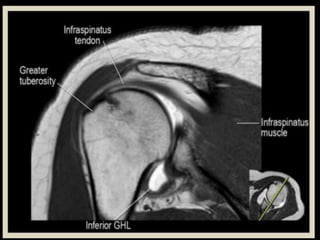

Shoulder

Joint.